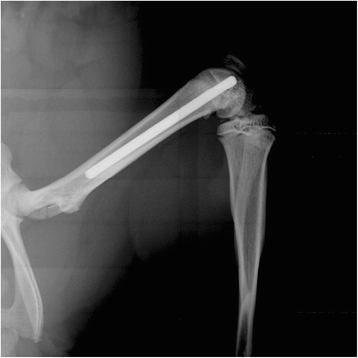

Methods: Titanium Kirschner-wires were implanted into the intramedullary canals of both femurs. Staphylococcus aureus, ranging from10(4) to 10(9) colony forming units, was injected into a tail vessel. After a designated time (3, 7, 14, or 42 days) the femurs were harvested and bacterial numbers determined for both the femur and the implanted K-wire. In addition, histology and micro-computed tomography were used as subjective tools to further characterize the infection.